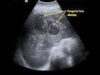

Liver abscess Types, Causes, Symptoms, Diagnosis Mediube Subscribe Subscribed 3 1173 videos 0% 41 Views 0 Likes 2025-01-20 Gastro intestinal By Mediube 0 Comments (بازدید 41 بار, بازدیدهای امروز 1 ) Show more PREV Differences between Diarrhea and Dysentery Mediube 2025-01-18 NEXT Pyogenic Liver Abscess Mediube 2025-01-27 You might be interested in 0 severe case of jaundice Mediube 2024-10-28 0 Understanding Appendicitis Mediube 2024-10-12 0 Eosinophilic Esophagitis Mediube 2024-07-03 0 Pyogenic Liver Abscess – General Surgery Mediube 2025-01-27 0 Jaundice Clinical Presentation Mediube 2024-10-19 0 Digestive System Infections Mediube 2025-03-17 0 Murphy Sign – Clinical Examination Mediube 2024-09-28 0 Anatomy of the abdominal viscera Liver, biliary ducts and gallbladder Mediube 2025-07-26 0 Understanding Stomas (Colostomy, Ileostomy, Urostomy and Gastrostomy) Mediube 2024-10-14 0 Purely laparoscopic left hepatectomy Mediube 2024-09-05 0 Jaundice Lab Tests – Urine Bilirubin Urobilinogen – How to diagnose jaundice (icterus) Mediube 2024-07-20 0 Physical exam findings for the work up of acute appendicitis Mediube 2024-09-28 LEAVE YOUR COMMENT Cancel replyYour email address will not be published. Required fields are marked * Save my name, email, and website in this browser for the next time I comment. Δ